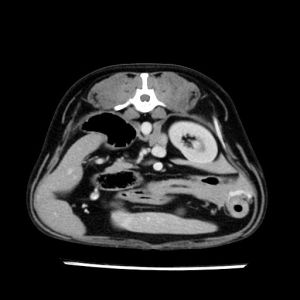

La lesione focale epatica , la ceus,la Tac e il chirurgo .